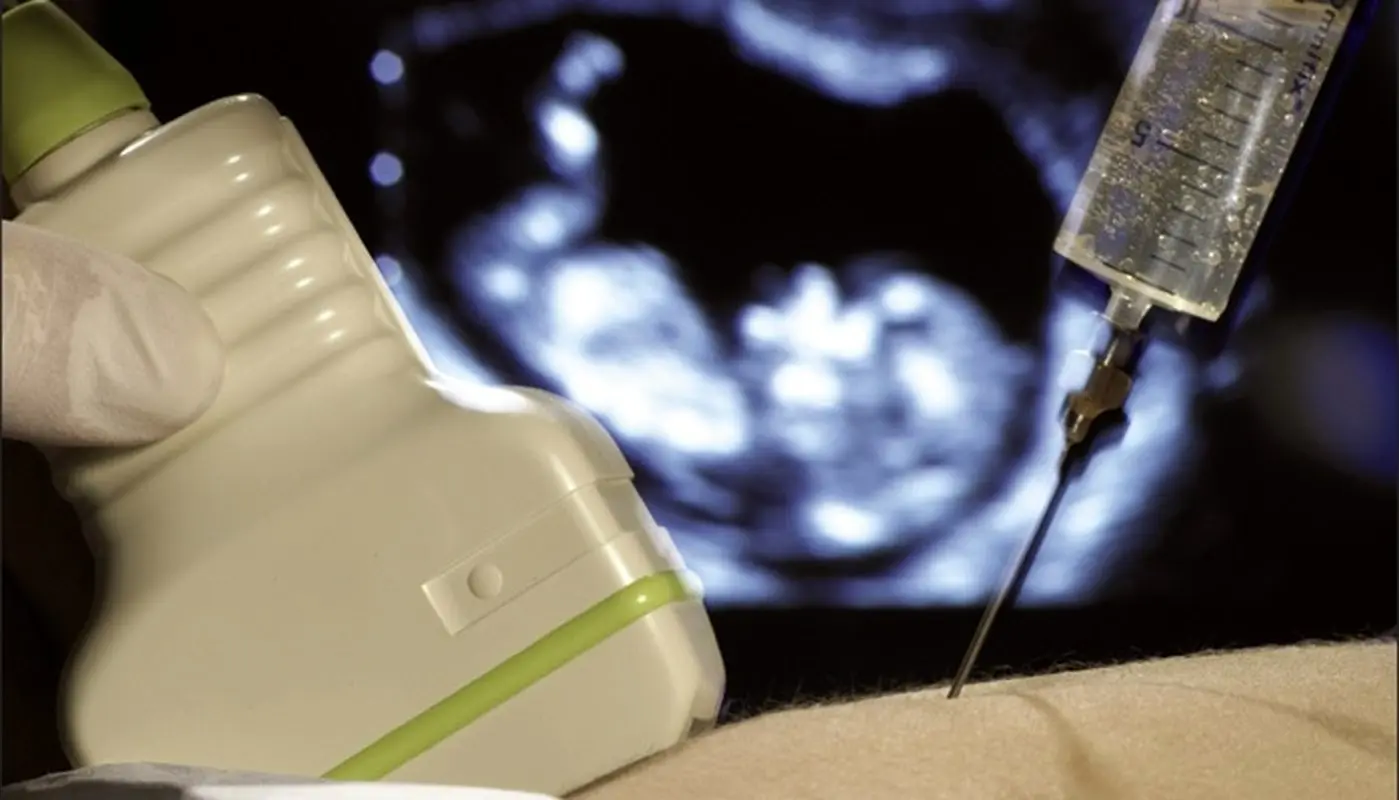

آزمایش آمنیوسنتز یکی از آزمایش های زمان بارداری است که با خارج کردن نمونه ای از مایع آمنیوتیک با سوزن از طریق شکم این کار انجام می شود که تحت نظارت سونوگرافی صورت می گیرد. حکم این مایه برای محافظت از جنین که دارای سلول های جنینی و مواد شیمیایی مختلف است که تحت انجام آزمایش آمینوسنتز از طریق سونوگرافی برای مشاهده حیات جنین و سن بارداری و تعداد جنین و ساختار بدن او مورد استفاده قرار می گیرد.

آزمایش آمنیوسنتز بیشتر در هفته های ۱۴ تا ۲۰ بارداری مورد انجام قرار می گیرد که تقریبا نیم ساعت زمان لازم دارد. بروز مشکل در والدینی که بتوانند مجوز سقط جنین را از پزشک قانونی بگیرند قبل از انجام آزمایش یک سونوگرافی از جنین در آناتومی انجام می شود. که مادر روی میز آزمایش دراز می کشد. از سونوگرافی برای تعیین محل دقیق نمونه گیری از کیسه آب استفاده می شود تا به جنین آسیبی نرسد که مدت انجام آن ۲۰ دقیقه می باشد. سپس پزشک یک سوزن بلند و نازک را از راه دیواره شکم وارد کیسه آب مادر می کند و با سونوگرافی فرآیندی را انجام می دهد.

بنابراین پزشک مقدار کمی مایع آمنیوتیک را توسط سرنگ خارج می کند و سوزن را بیرون میآورد. خارج کردن مایع ممکن است چند دقیقه طول بکشد اما کمتر از ۳۰ ثانیه زمان میبرد. برای جایگزینی مایع خارجشده دور جنین دوباره مقداری مایع خواهد ساخت. این کار ممکناست کمی کوفتگی و خستگی یا فشار ایجاد کند و شاید هیچ احساسی هم وجود نداشته باشد. درد در زنان باردار متفاوت است که با انجام این آزمایش به شکم حتی بارداری های اول و دوم و غیره انجامش متفاوت است و باید قبل آزمایش شکم بی حس شود. در برخی موارد درد بی حسی از درد آزمایش آمنیوسنتز بیشتر است که در پایان پزشک ضربان قلب جنین را مورد بررسی قرار می دهد.